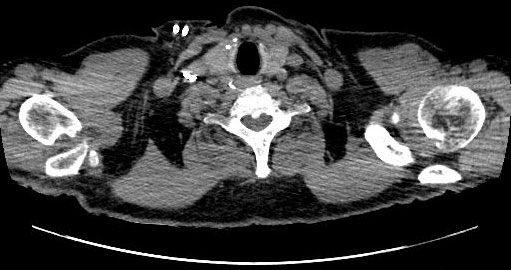

L'intensité de la douleur vertébrale évoquait principalement 3 diagnostics : une spondylodiscite infectieuse étant donné le terrain immuno-déprimé, une pathologie micro-cristalline fréquente chez le dialysé et en 3ème position, une fracture vertébrale qui était rapidement éliminée par l'imagerie.

La CRP et la NF normales étaient contre une infection, tous les prélèvements étaient stériles. Sur le scanner on croyait voir une image calcique sur le ligament vertébral postérieur.

Le dossier a été présenté au staff et sur le viewer de Lariboisière les images de calcification du ligament vertébral postérieur étaient beaucoup plus visibles,